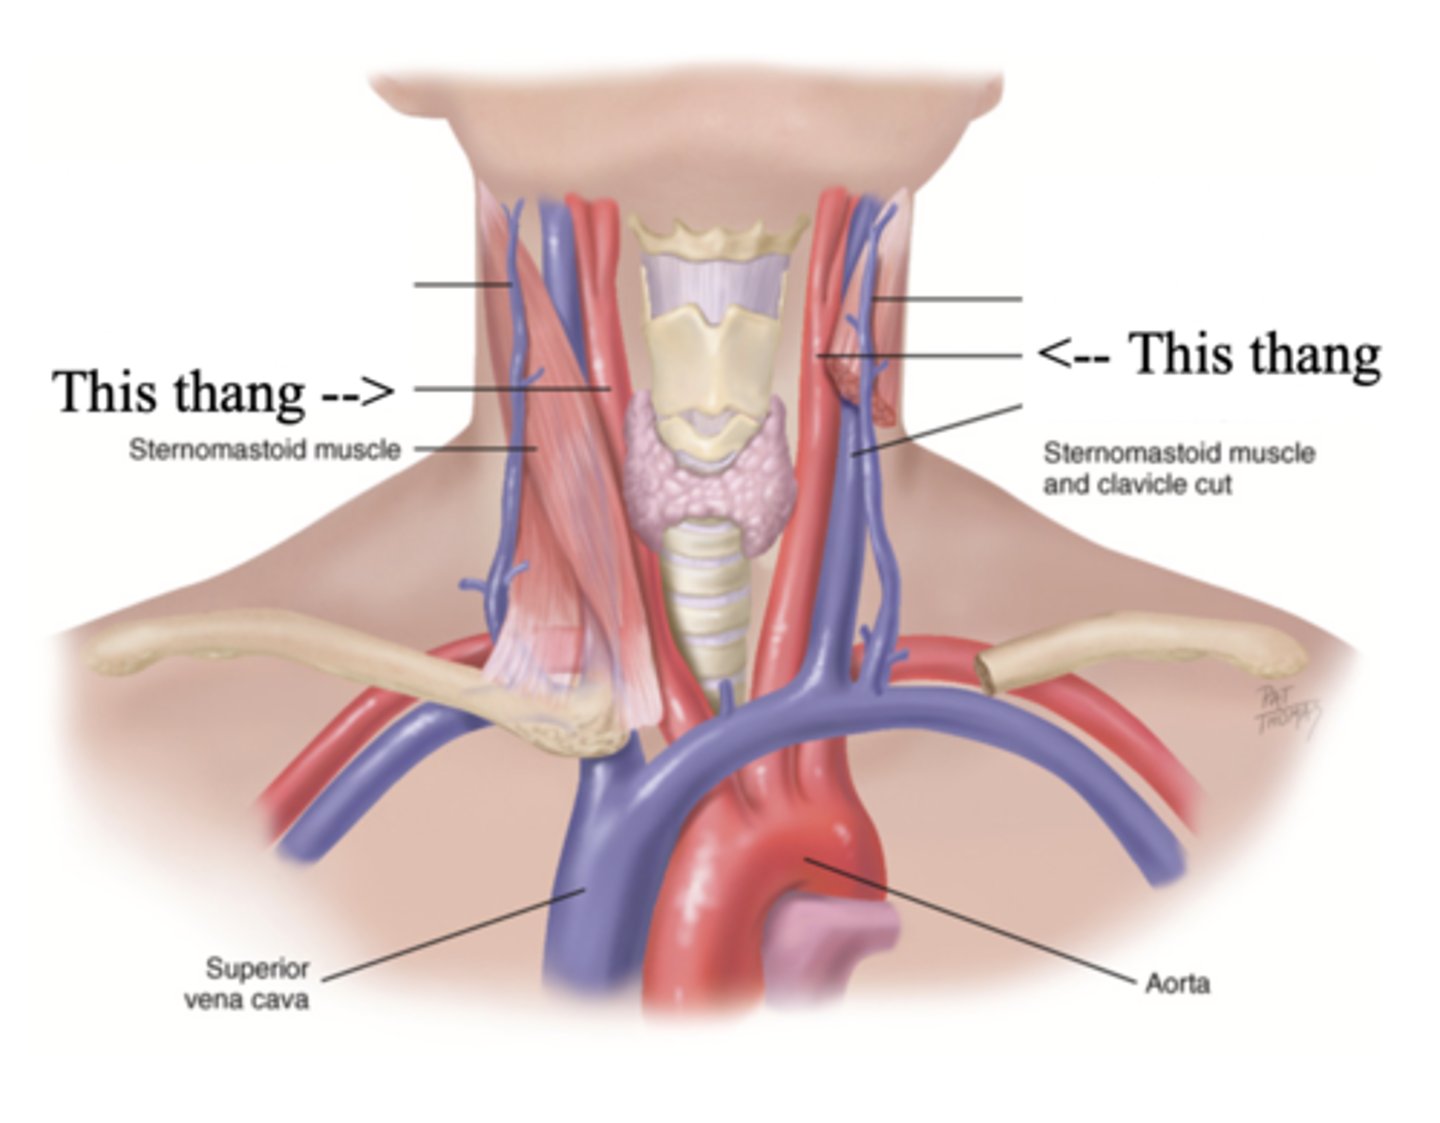

2 Main Neck Vessels

- Jugular veins

- Carotid arteries

Jugular Veins

- One of the main neck vessels; carries unoxygenated blood to the superior vena cava

- Has 2 parts

- Provides information about activity of right side of heart

2 Parts of the Jugular Veins

- External

- Internal

External Jugular Veins

The more superficial jugular vein that lies lateral to the sternocleidomastoid and above the clavicle

Internal Jugular Veins

The deeper jugular vein that lies medial to the sternocleidomastoid

Carotid Arteries

The major neck vessel that carries oxygenated blood from the heart to the head

Main Differences Between Internal Jugular Veins and Carotid Arteries

- Internal jugular pulse more lower and lateral to sternocleidomastoid than the carotid pulse, which is higher and more medial

- Internal jugular pulse is more undulant and diffuse, while carotid pulse is more brisk and localized

- Internal jugular pulse varies with respiration

- Carotid pulse can be palpated

- Palpating internal jugular pulse will obliterate it

- Internal jugular pulse drops/disappears as the patient is brough to a sitting position